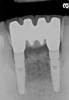

Figure 2  Preoperative radiograph shows healthy cuspids and advanced periodontal disease on the four mandibular incisors.

Figure 2